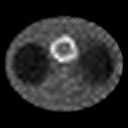

From the observations of figures 5 and 6, and table 2,

we can draw the same conclusions as the experiment 1.

Comparing figures 3 and 5,

we can see that the visual quality of the images reconstructed from data set 2

are inferior to those reconstructed from data set 1

because of the low count level.

And the performance of the superiorized EM algorithms 2 are much more remarkable than the superiorized EM algorithms 1 for data set 2.

Comparing the results of the two experiments above, we can observe that

the TV-superiorized EM algorithm 2 is better in terms of RMSE, while the -superiorized EM algorithms 2

in terms of TV and -norm values. In addition, the thresholding operations cause the Gibbs oscillations in the reconstructed images by -superiorized EM algorithms 2.

Because the detectors rotated from top to bottom through

left side, the gamma rays emitted from the right part pixels are more likely to

be absorbed. Therefore,

the right part of the reconstructed images are blurred strongly(see figures 2, 3 and 5).